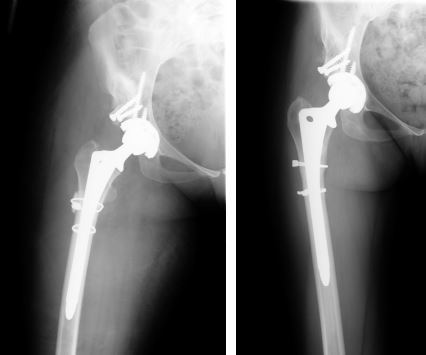

方法:在一项回顾性研究中,我们评估了24例非骨水泥全髋关节置换术的结果和并发症,共 24例(20例女性和4例男性)Crowe型IV型发育不良。采用非骨水泥全髋关节置换术结合转子下缩短截骨术,将髋臼假体放置在解剖学旋转中心的水平处。术后平均随访4.8年,对患者进行评估。

结果:平均的Harris髋关节评分从术前的 43 分提高到了最终随访时的 89 分(p <0.01)。 28 个髋中有12个(43%)发生了早期或晚期并发症或再次手术。28例转子下截骨术中有2例(7%)发生骨不连。有1例股骨柄松动,1个髋臼假体松动,1个髋臼内衬脱离。术后有4例髋关节脱位。在最后一次随访时,其余组件均固定良好。未发现坐骨神经损伤的病例。

结论:在髋关节发育不良继发高位髋关节脱位的患者中,非骨水泥全髋关节置换术结合股骨转子下缩短截骨术可以成功固定植入物和获得截骨部位愈合,平均术后Harris髋关节评分89分。 然而,这一类患者术后的并发症发生率显著高于骨关节炎的初次全髋关节置换术。